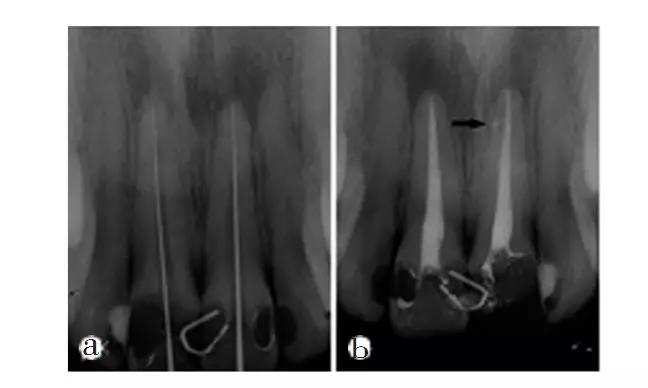

正確的牙髓活力判斷決定了臨床治療計(jì)劃的合理性。目前臨床上測(cè)試牙髓活力的方法有感覺(jué)測(cè)試和血流測(cè)試,并且主要是電測(cè)試、溫度測(cè)試等感覺(jué)測(cè)試。血流測(cè)試由于技術(shù)和成本問(wèn)題目前并未廣泛應(yīng)用于臨床,沒(méi)有一種牙髓活力測(cè)試方法臨床上能夠準(zhǔn)確判定患牙牙髓活力狀態(tài)。有研究表明,聯(lián)合運(yùn)用冷測(cè)和電測(cè)可提高測(cè)試結(jié)果的準(zhǔn)確性。為了臨床上更好的判斷牙髓活力狀態(tài),并獲得準(zhǔn)確的判斷結(jié)果,特提出牙髓活力狀態(tài)判斷的臨床路徑和操作規(guī)范,供大家參考。